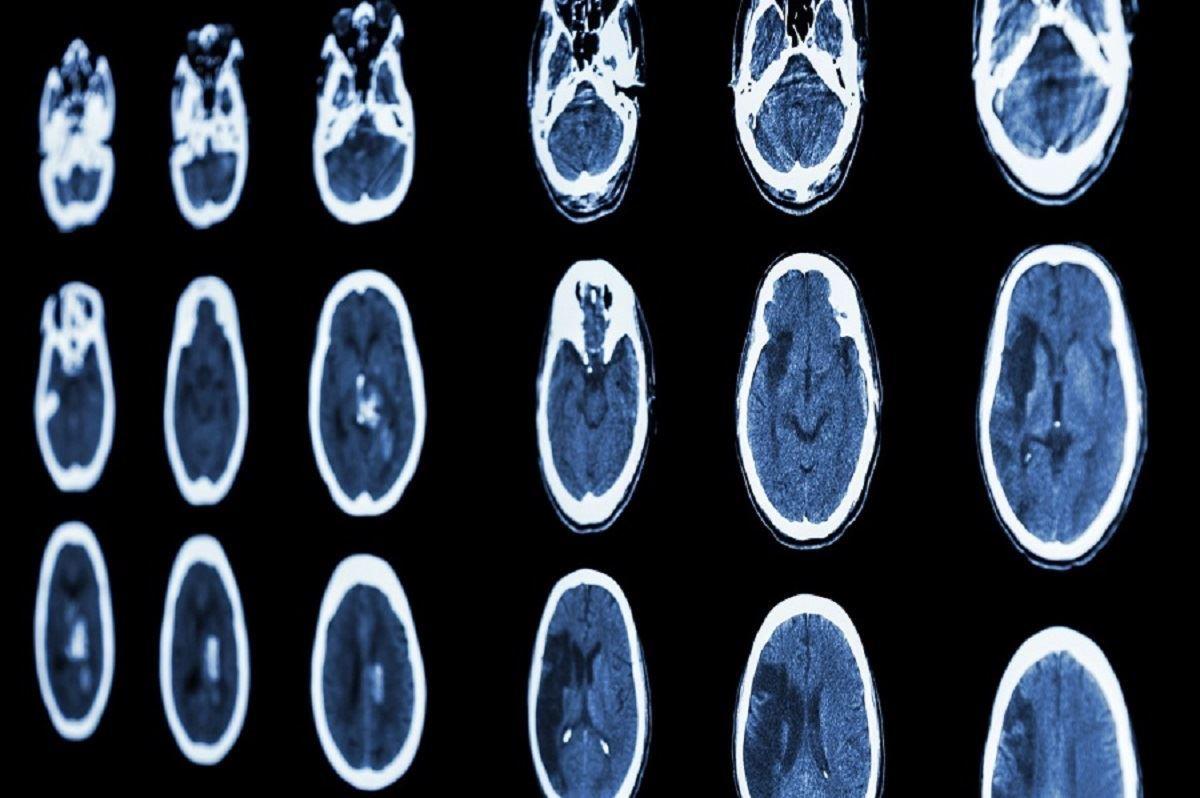

دانشمندان برای انجام این کار، از داده‌های بیش از 2500 فرد 30 تا 94 ساله استفاده کرده‌اند که شامل تجزیه‌و‌تحلیل حجم مغز و ضخامت قشر آن از طریق MRI و ارزیابی فعالیت بدنی آن‌ها می‌شود. همچنین شرکت‌کنندگان در این آزمایش مجبور شدند تا به مدت هفت روز روی ران خود یک شتاب سنج پوشیدنی را متصل کنند.

در ادامه آن‌ها متوجه شدند که فعالیت بدنی تاثیر قابل‌توجهی بر تقریبا تمام مناطق مغز انسان‌ها دارد. فاکس توضیح می‌دهد: «‌به‌طور کلی، می‌توان گفت هرچه فعالیت بدنی بیشتر و شدیدتر باشد، مناطق مغز از نظر حجم یا ضخامت قشر مغز بزرگتر است. به‌ویژه، ما این مورد را در هیپوکامپ مشاهده کردیم که مرکز کنترل حافظه در نظر گرفته می‌شود.»